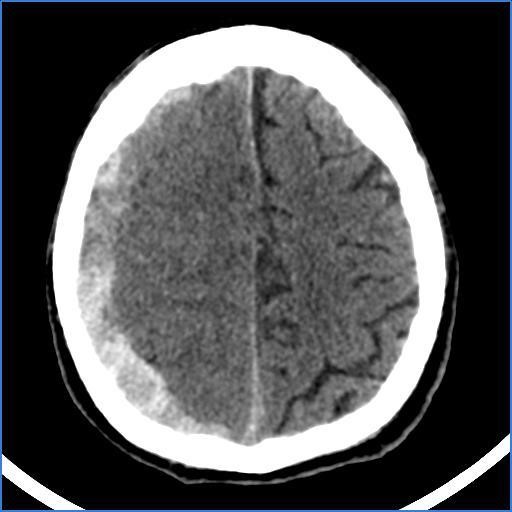

Apresentação do caso clínico

Paciente de sexo masculino, 60 anos de idade e etilista foi admitido ao Hospital de Trauma de Campina Grande na Paraíba com perda da consciência no dia 23/10/2019. O paciente foi atendido pelo neurocirurgião de plantão que, após a avaliação neurológica, solicitou uma tomografia computadorizada sem contraste do encéfalo do paciente. O resultado desse exame foi analisado pelo neurocirurgião que constatou o quadro de hematoma subdural de repetição localizado à direita, comprimindo importantes áreas do encéfalo.

As imagens da

tomografia acima indicam que houve um ressangramento das veias presentes no

espaço subdural. Esse acúmulo de sangue gerou um efeito de massa que levou o

paciente a repercussão clínica neurológica de perda de consciência.

2. Em pacientes com

hematoma subdural, o sangue das veias subdurais se acumula no extenso espaço

subdural, uma cavidade virtual entre a camada meníngea da dura-máter e a

aracnoide-máter, produzindo uma borda de

sangue hiperdenso com formato côncavo-convexo semelhante a uma banana, como

evidenciado nas imagens antes da cirurgia. Com um hematoma grande, os sulcos

cerebrais são obliterados, ficando menos evidentes, e as estruturas na linha

média são desviadas para o lado oposto